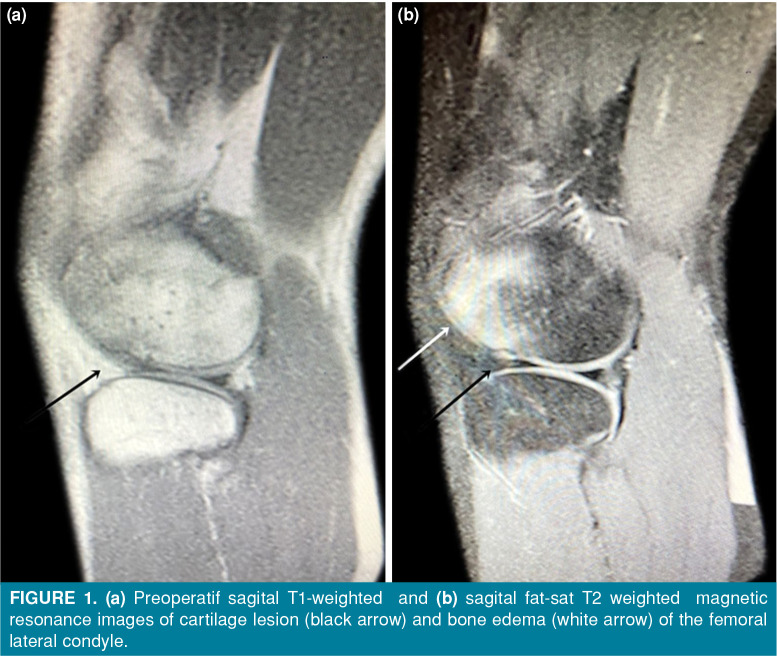

Patients and methods: Between January 2011 and January 2020, a total of 34 patients (19 males, 15 females; median age: 15.6 years; range, 13 to 17 years) with RPD who underwent anatomic MPFL reconstruction were retrospectively analyzed. Lateral release was performed as indicated. Clinical outcomes were evaluated preoperatively and at the final follow-up using the Visual Analog Scale (VAS), Lysholm, Kujala, and Tegner activity rating scales. Magnetic resonance imaging was performed to detect concomitant injuries such as bone, cartilage, and soft tissue injuries.

Results: The mean follow-up was 5±2 years. All postoperative knee functions and activity levels were statistically significantly improved without re-dislocation (p<0.001). There was no statistically significant relationship between the presence and location of cartilage lesions and clinical outcomes (p>0.05). Patients with cartilage lesions had a significantly higher CatonDeschamps index and a higher incidence of bone edema in both the patella and femur than patients without.